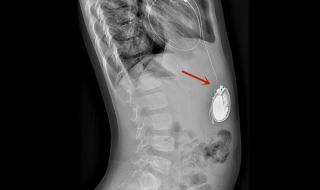

全磁浮人工心脏介绍 男子植入最小人工心脏

全磁浮心脏即离心泵人工心脏,被称为第三代人工心脏,是目前最先进,对人体影响最小也是最耐用的人工心脏,美国FDA前两年刚上市了第一款,我国高端医疗器械几乎无国产产品。

男子植入最小人工心脏